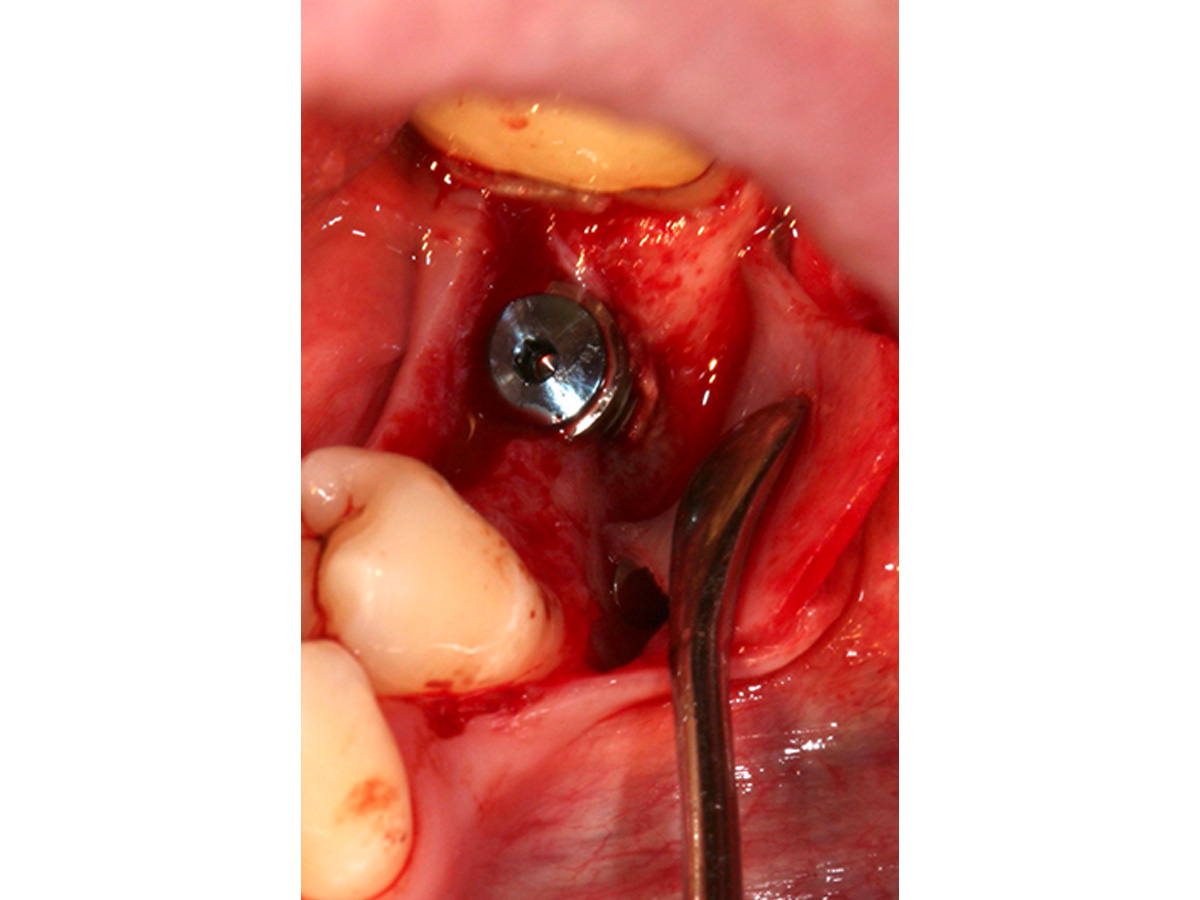

Nach Implantation wurde die zugeschnittene Bone Lamina positioniert und mit Pins fixiert, die Situation danach ist in Abb. 5 zu sehen. Mit dem Instrument wird demonstriert, dass eine „Tasche“ geschaffen wurde, die in Abb. 6 mit mp3® Knochengranulat aufgefüllt wird. Abb. 7 stellt dar, wie die Bone Lamina über den Kopf des Implantates auf den lingualen Anteil des Kieferkammes positioniert wird.

Nach Implantation: Positionierung und Fixierung der Bone Lamina.

Abbildung 5